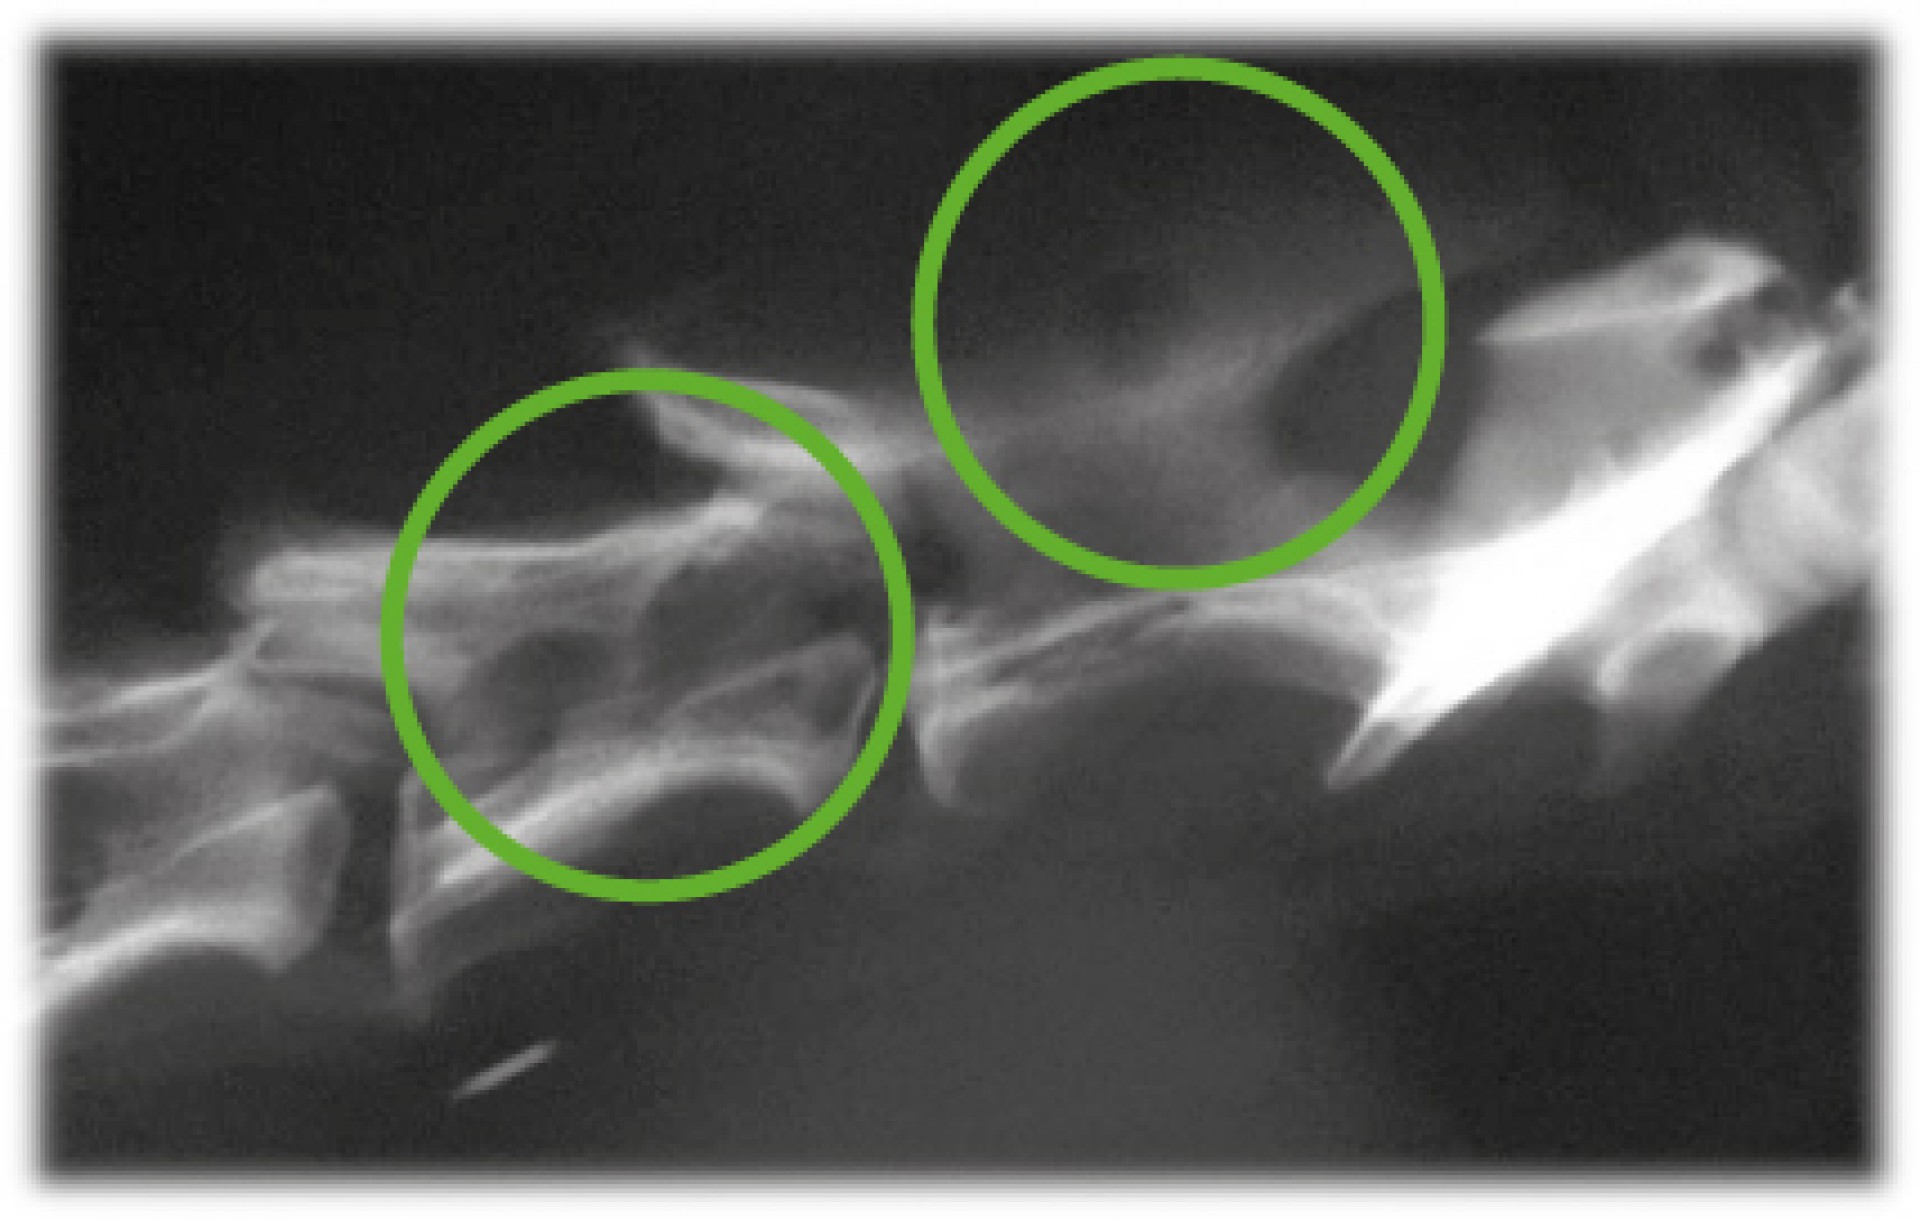

Míg az utóbbi esetben az elsődleges daganat eltávolítását, szövettani vizsgálatát követően az áttétes daganatok kemoterápiás/ sugárterápiás gyógykezelési lehetősége merül fel elsődlegesen, addig a primer gerincdaganatok kialakulása esetén annak pontos lokalizációját, a gerincoszlop alkotóelemeinek érintettségének maghatározását követően a daganat műtéti eltávolítására is sor kerülhet.A klinikai tünetek kialakulása sokféle lehet, szinte minden esetben egy folyamatosan rosszabbodó, idegrendszeri tünetek súlyosbodásával járó, gyakran azonos oldali mellső és hátsó végtagot érintő neurológiai kiesést tapasztalunk. A klinikai tünetek alapján azonban a gerinc daganatos megbetegedései nem különíthetőek el a hasonló kórlefolyású degeneratív megbetegedésektől (pl.: porckorongsérv). Így a diagnózis pontos felállításához kiegészítő vizsgálatokra mindenképpen szükség van. Ezek közé tartozik a natív röntgenvizsgálat, de mivel a gerincvelő környéki, a csontvázat nem érintő daganatok többnyire nem adnak röntgenárnyékot, ezért az egyszerű röntgen vizsgálaton túl egyéb képalkotó eljárásokra, kiegészítő vizsgálatokra is szükség lehet.